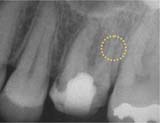

■異物の除去■

施術前

異物

施術後

「施術前」の写真は、他院から紹介で受診された患者さんのものです。治療中には不測の事態が起きることがあります。

写真には治療用の器具が写っています。

折れた器具を技術を駆使して取り去り、通常通り根を薬で詰めて治療は完了します。